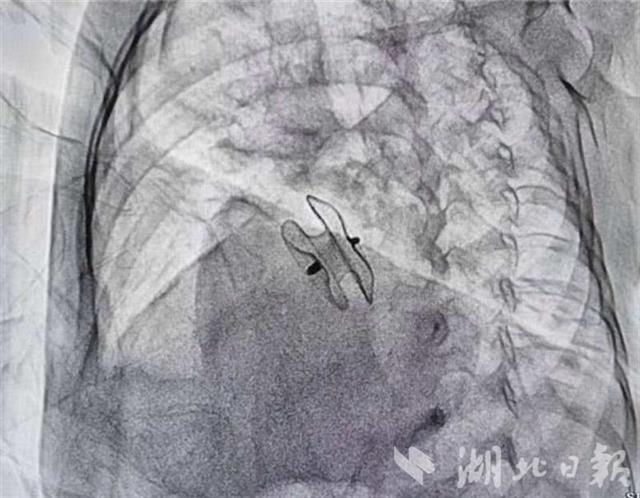

“孩子实在是不能等了,我只能试一试。”7月20日,李翔带着女儿小梦到武汉儿童医院来求诊。得知小梦家庭贫困,武汉儿童医院将她纳为“爱佑童心”爱心项目的资助对象。该院心血管内科主任张勇通过微创介入方式,成功将缺损牢牢堵住。7月25日,小梦康复出院。

李翔介绍,小梦全部费用4万余元,医保报销近一半,剩下的部分由救助基金兜底承担绝大部分,自己几乎零负担。